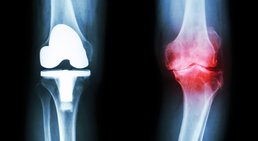

Künstliches Kniegelenk (Knieprothese)

Eine Knieprothese bzw. ein künstliches Kniegelenk ist dann indiziert, wenn das eigene Knie verschlissen und abgenutzt ist. In über 90% der Fälle ist eine...